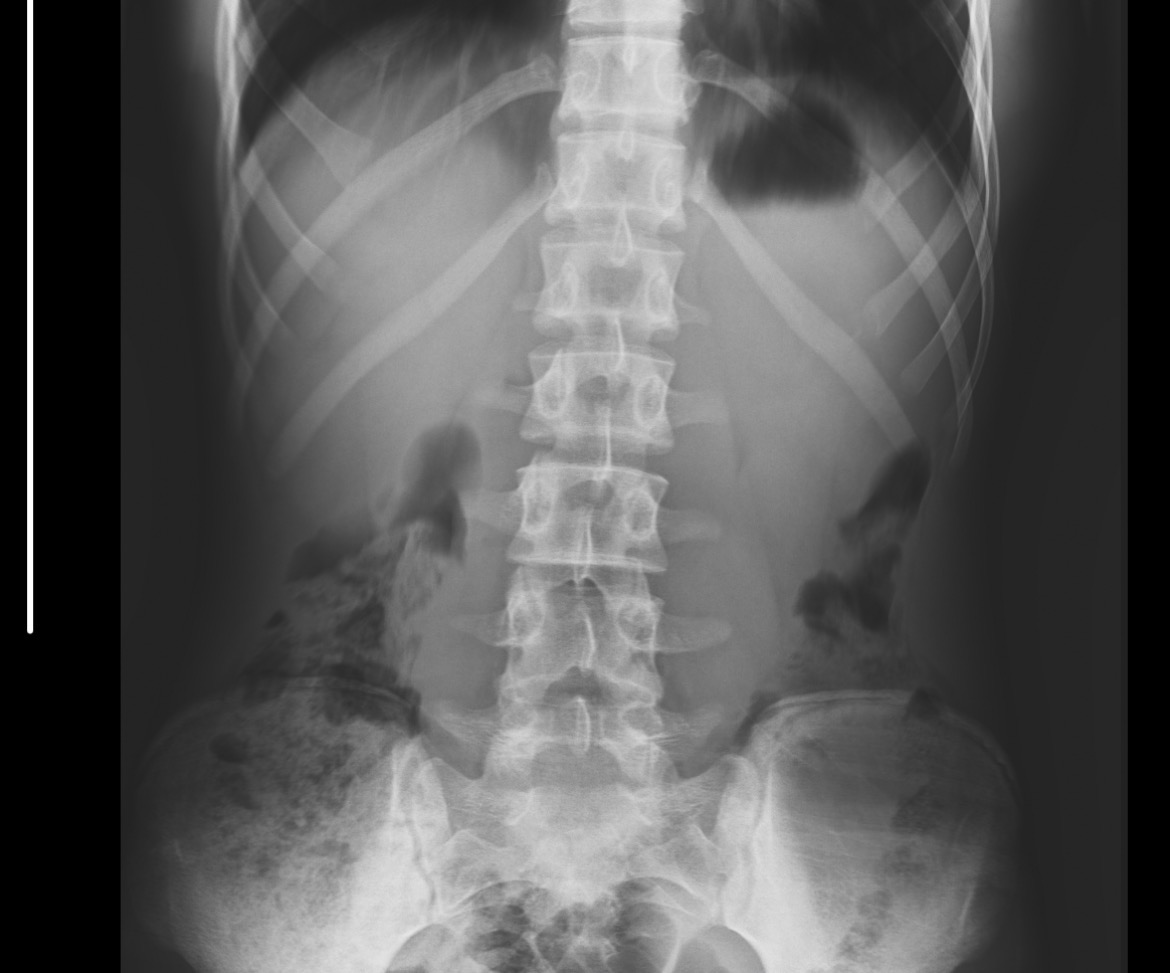

Ne diyonuz açık kapalı

parmaktakiler kapalı ama düzgün röntgen yok mu böyle emin değilim

Açıkla Karşılaştırma yaptımda kapalı diye yorumladım dize baktırcam artık bidahaki röntgende

Kalça kemiğinden anlaşılıyor sanırım bide atsam bi bakarmısın?

kalça kemiği bildiğim kadarıyla ergenliği geçmiş kişilerd ekemik yaşı tayinini daha rahat yapabilmek için. çok anlamam ama femurun üst kısmı kapalı mı değil mi diye at yine de bi. alt kısım daha geç kapanıyor ama

over knk kapalı

IMG 2510

Böyle aga kısmen gözüküyor bana kalsa boydan çekerimde çekmiyorlar işte

çok anlamıyorum kalçadan dediğim gibi. bacağın üstü de vardır sandım

xray lateral olsaydı belki apofiz plaklarına bakılırdı. burası genelde yetişkin birisi için falan adli falan bi şeyler kemik yaşı istenirken çekiliyor

Açıkmış kanka bu arada aldığım bilgi urlde Url